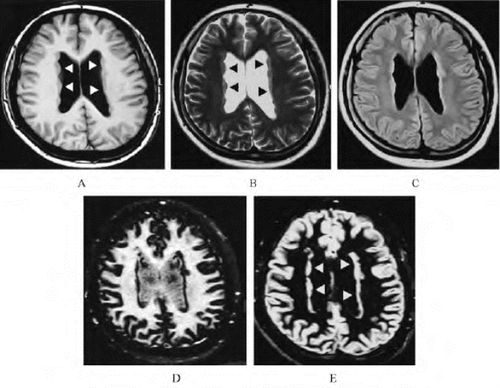

脑灰质异位,脑灰质异位图片

脑灰质异位_人体磁共振成像解

典型病例-脑灰质异位症

脑灰质异位症1例

脑灰质异位

医影学堂丨八个病例带你看懂脑灰质异位的三种类型